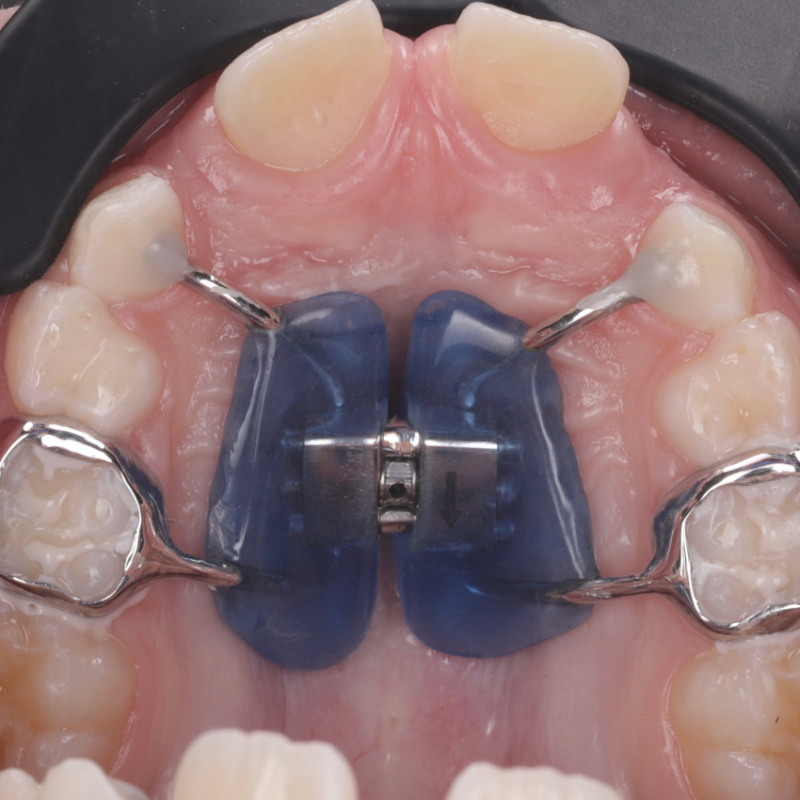

- Если верхняя челюсть ребенка слишком узкая, зубам не хватает места. Ортодонт может увидеть это у ребенка в шесть-семь лет — с появлением первых постоянных зубов. Установка аппарата в этом возрасте поможет расширить верхнюю челюсть. В более позднем возрасте приходится решать проблему другими путями, например удалением зубов.

Например, если у ребенка не хватает места для прорезывания всех зубов. В семь-восемь лет ему можно поставить брекеты, но не на все зубы, а только на четыре передних и два дальних. Между этими брекетами устанавливают пружину, которая расталкивает зубы.

Еще брекеты устанавливают до полной смены зубов для стимуляции роста нижней челюсти. Здесь врач может использовать брекеты вместе с несъемным аппаратом либо только съемный аппарат. Последний не так эффективен: результат сильно зависит от того, соблюдает ли ребенок режим ношения.

В такой ситуации брекеты можно использовать, даже если зубы еще не поменялись, потому что важно не упустить пик роста, после которого изменить размер челюсти можно только хирургическим путем.